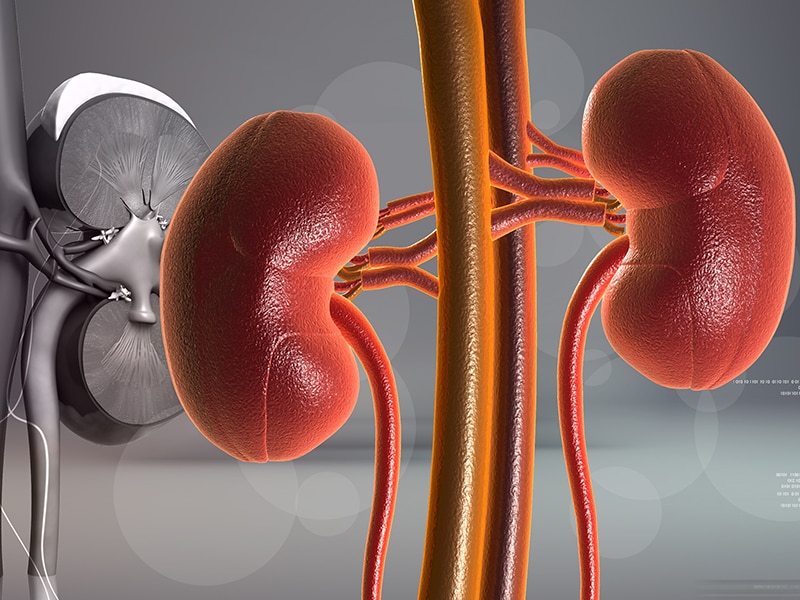

Строение почек человека: Фото и описание